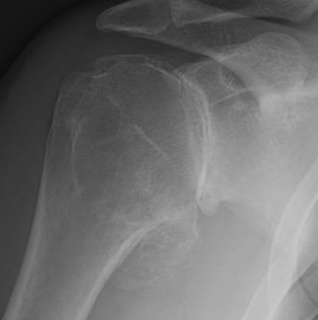

Here is the preop film of a man in his mid forties who came from California for us to perform a ream and run procedure on his right shoulder.